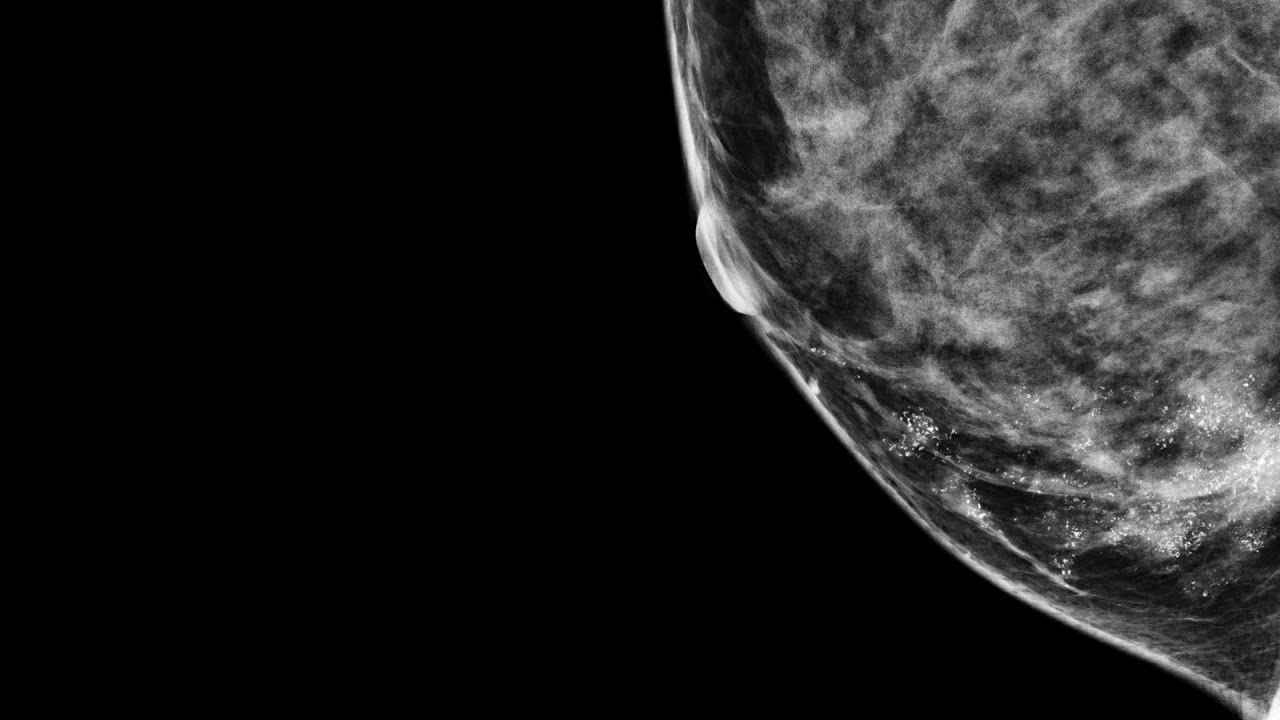

At Stanford, we offer you the most advanced diagnosis and treatment techniques for breast cancer, no matter how common or complex your cancer type. Our program is a major referral center for women and men across the country.